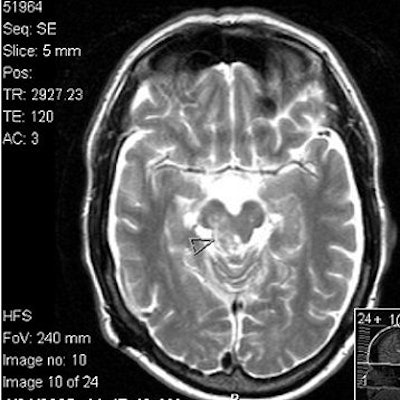

![]() |

Above, T1-weighted postcontrast axial image from the MRI series undergone by Dena Schlosser. Below, an axial diffusion-weighted image. Schlosser's neurologist examined Schlosser after her first trial and, based on the MRI exam, testified that midbrain injuries could cause visual hallucinations. Schlosser had previously told psychiatrists that she believed God wanted her to cut off her child's arms, as well as her own arms, legs, and head (Dallas Morning News, April 3, 2006). Images courtesy of David K. Haynes, Attorney at Law.